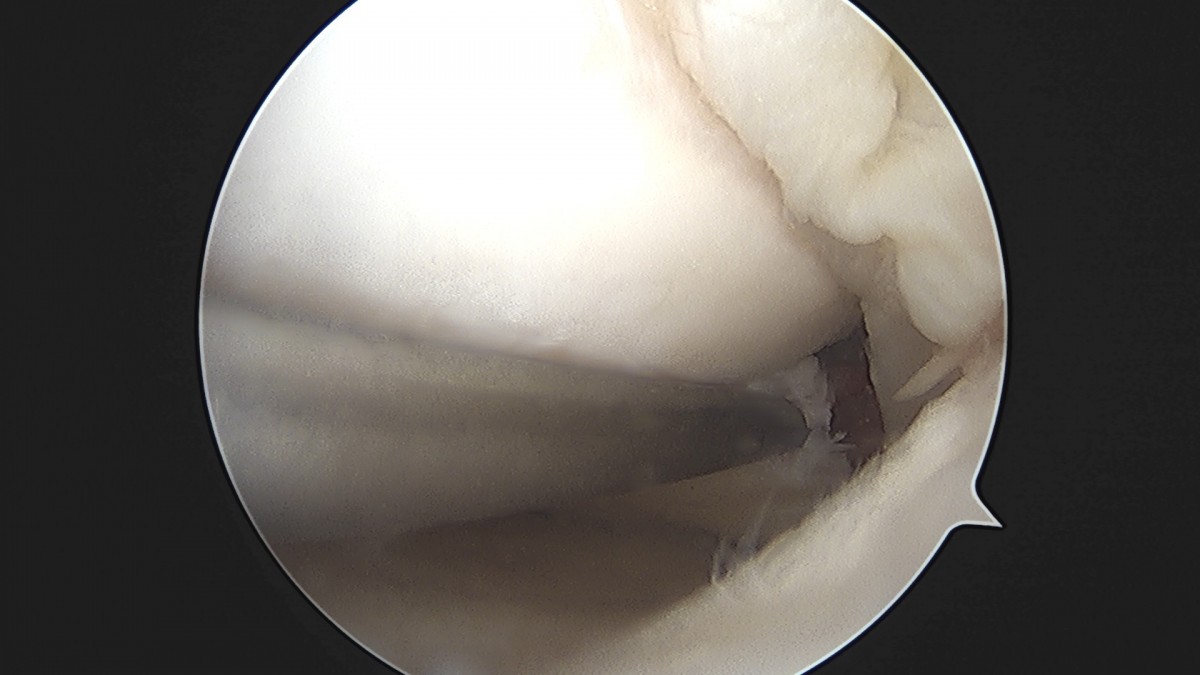

이재상원장님 무릎 낭종 제거술 김은O 환자

작성자 최고관리자 댓글 0건 조회 789회 작성일 25-09-16 15:20